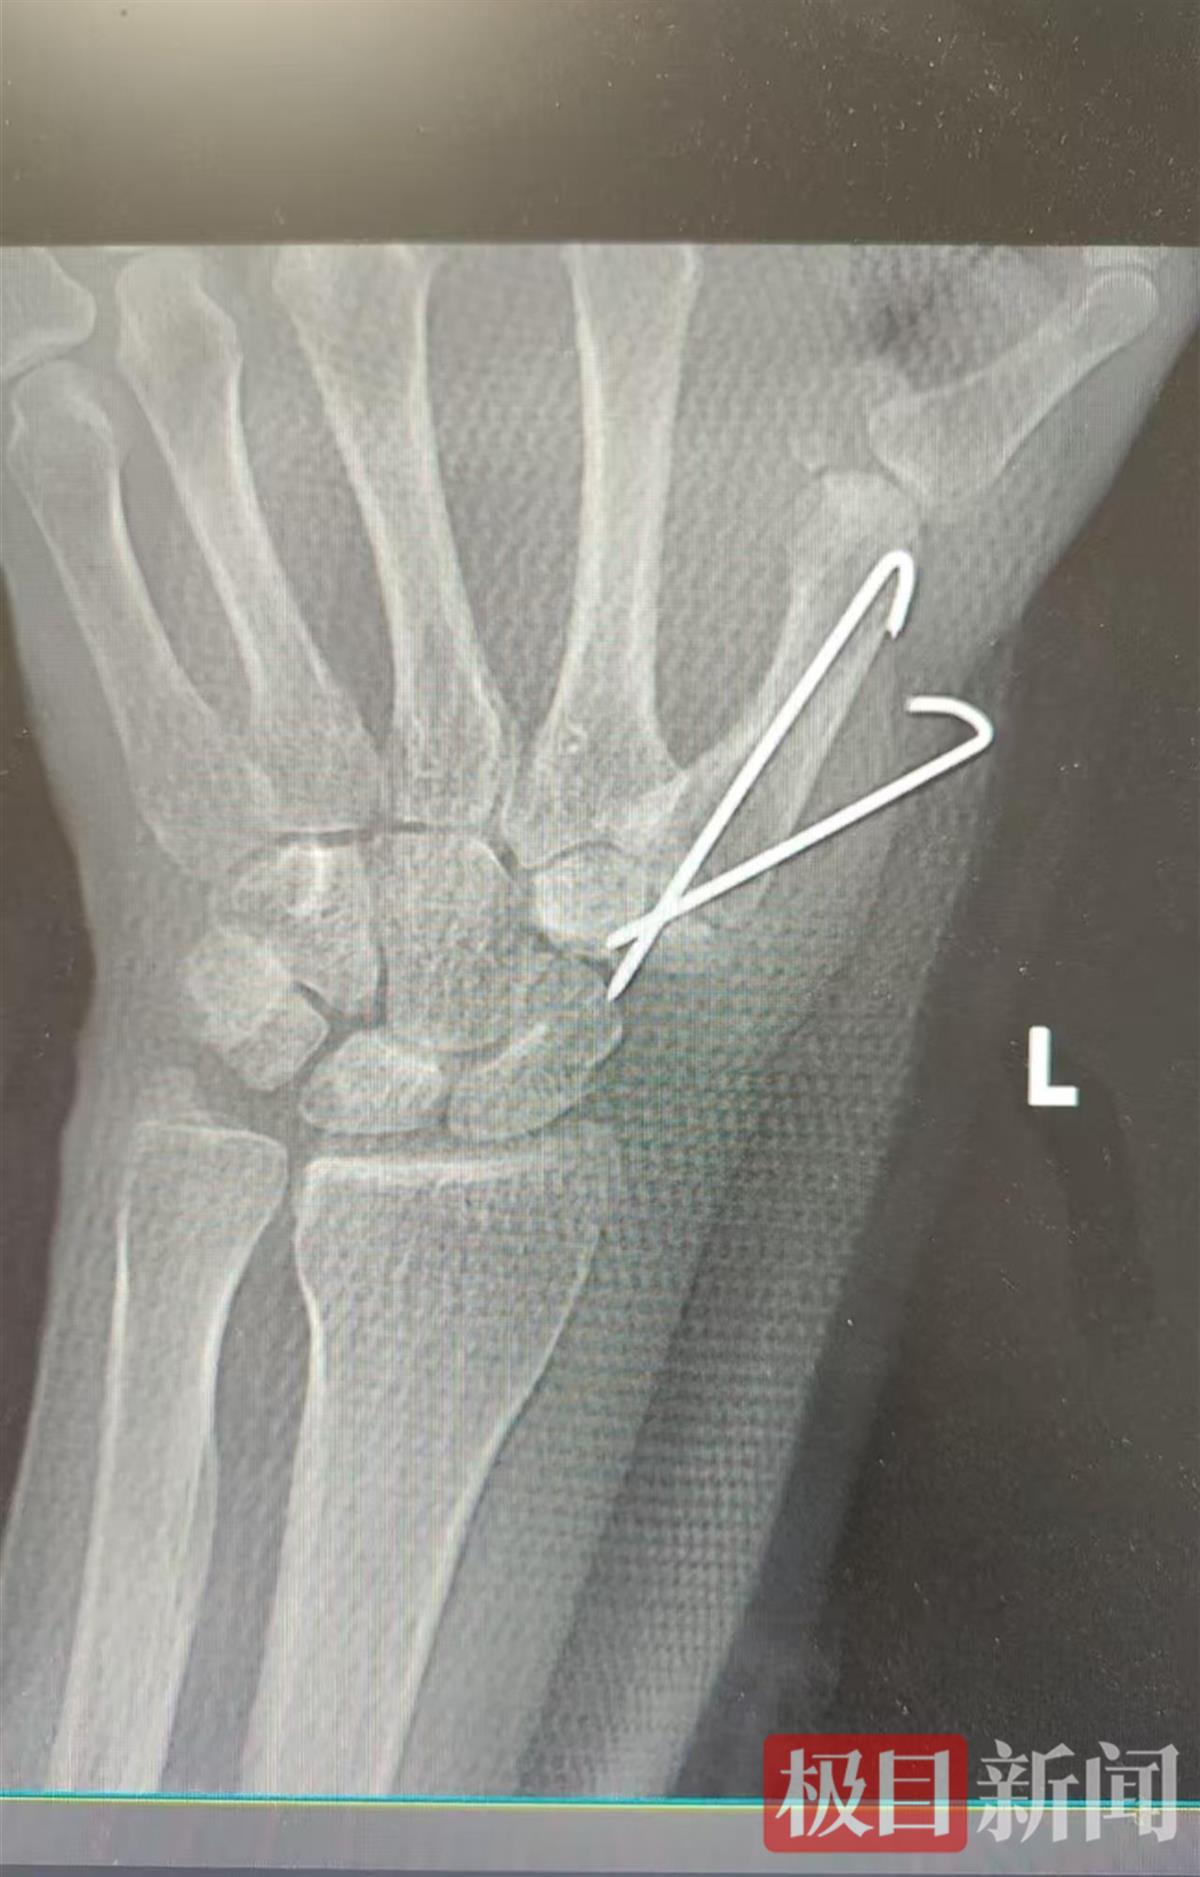

手术后影像图

早期的关节脱位可以通过手术进行干预,稳定关节,但遗憾的刘女士已经发展成为终末期关节炎,无法再保留关节和活动度。医生最终为其制定了腕掌关节融合的治疗方案,术后刘女士恢复良好,拇指的疼痛消失。